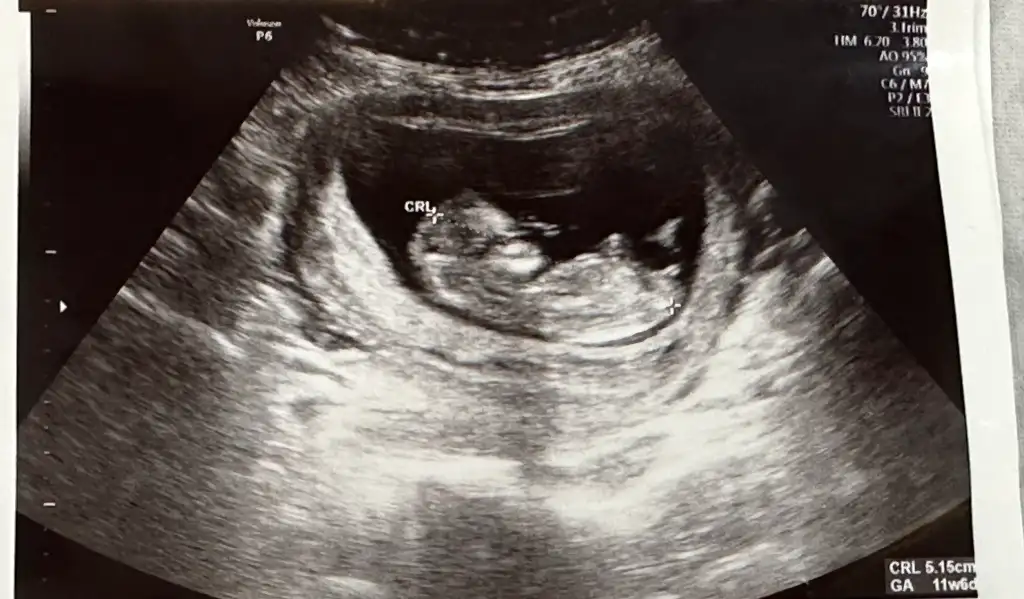

Bende merak ediyorum tahmini olan var mı ☺️

Ayy beni de sora bilirmisiniz acaba? Tahmin var ama merak etdim ne diyeceğini)